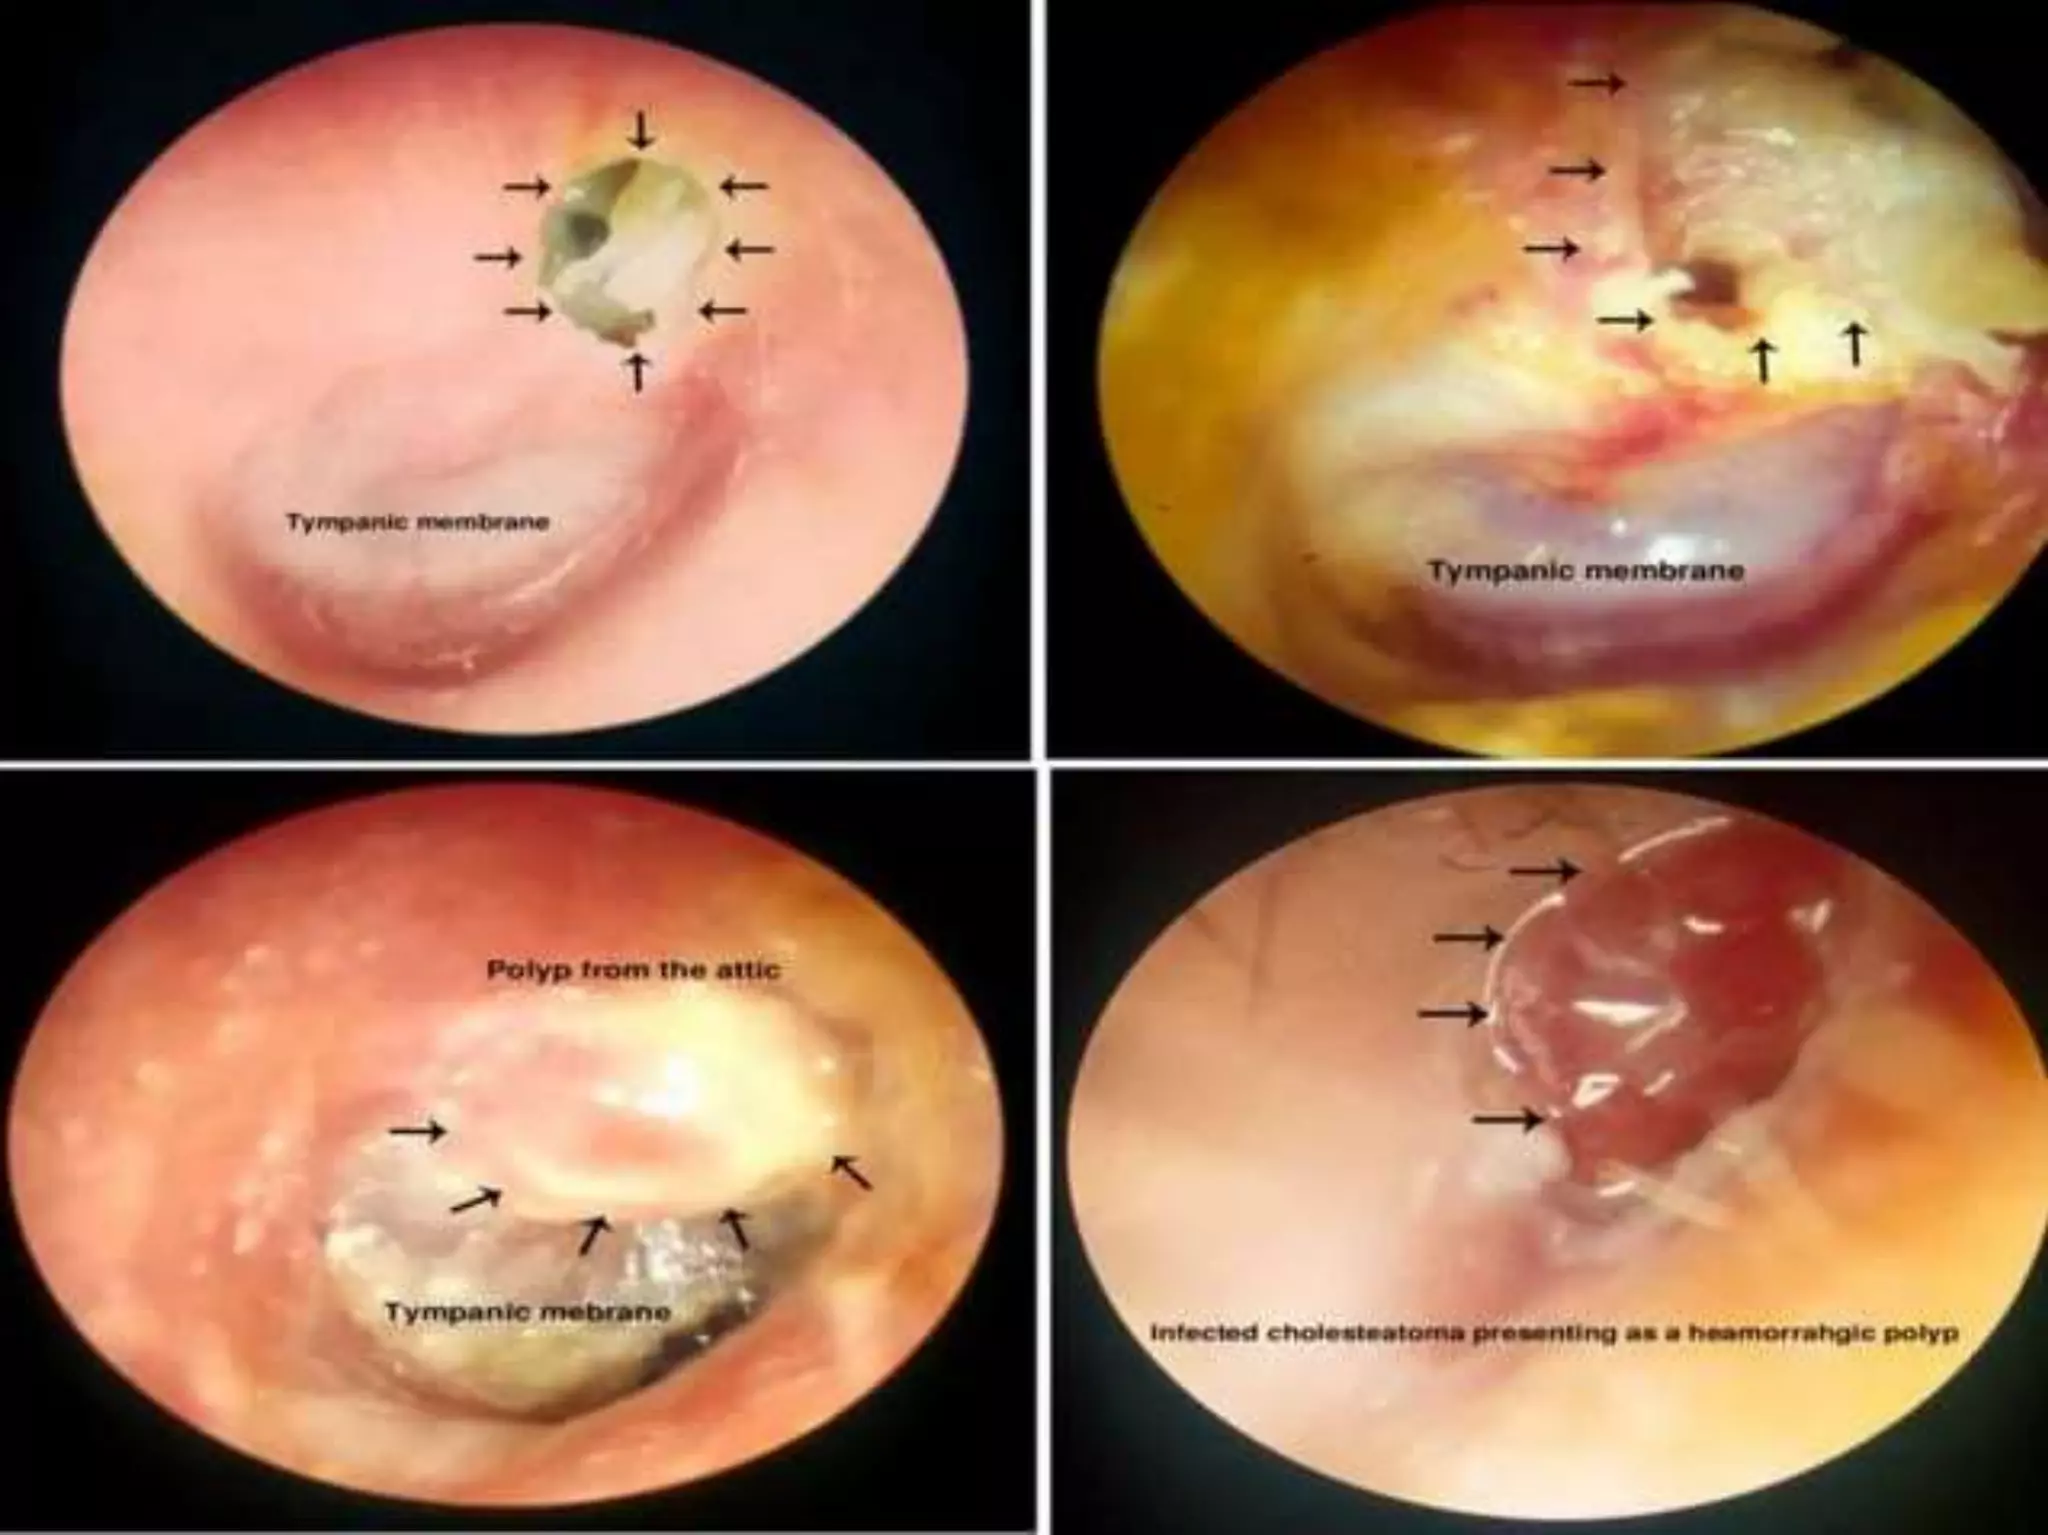

Chronic otitis media is a chronic inflammation of the middle ear and mastoid cavity that presents with recurrent ear discharge through a perforated eardrum. It has several subtypes depending on the state of the eardrum perforation and epithelium. It can be caused by prior acute otitis media, genetics, environment, eustachian tube issues, gastroesophageal reflux disease, craniofacial abnormalities, or immune deficiency.